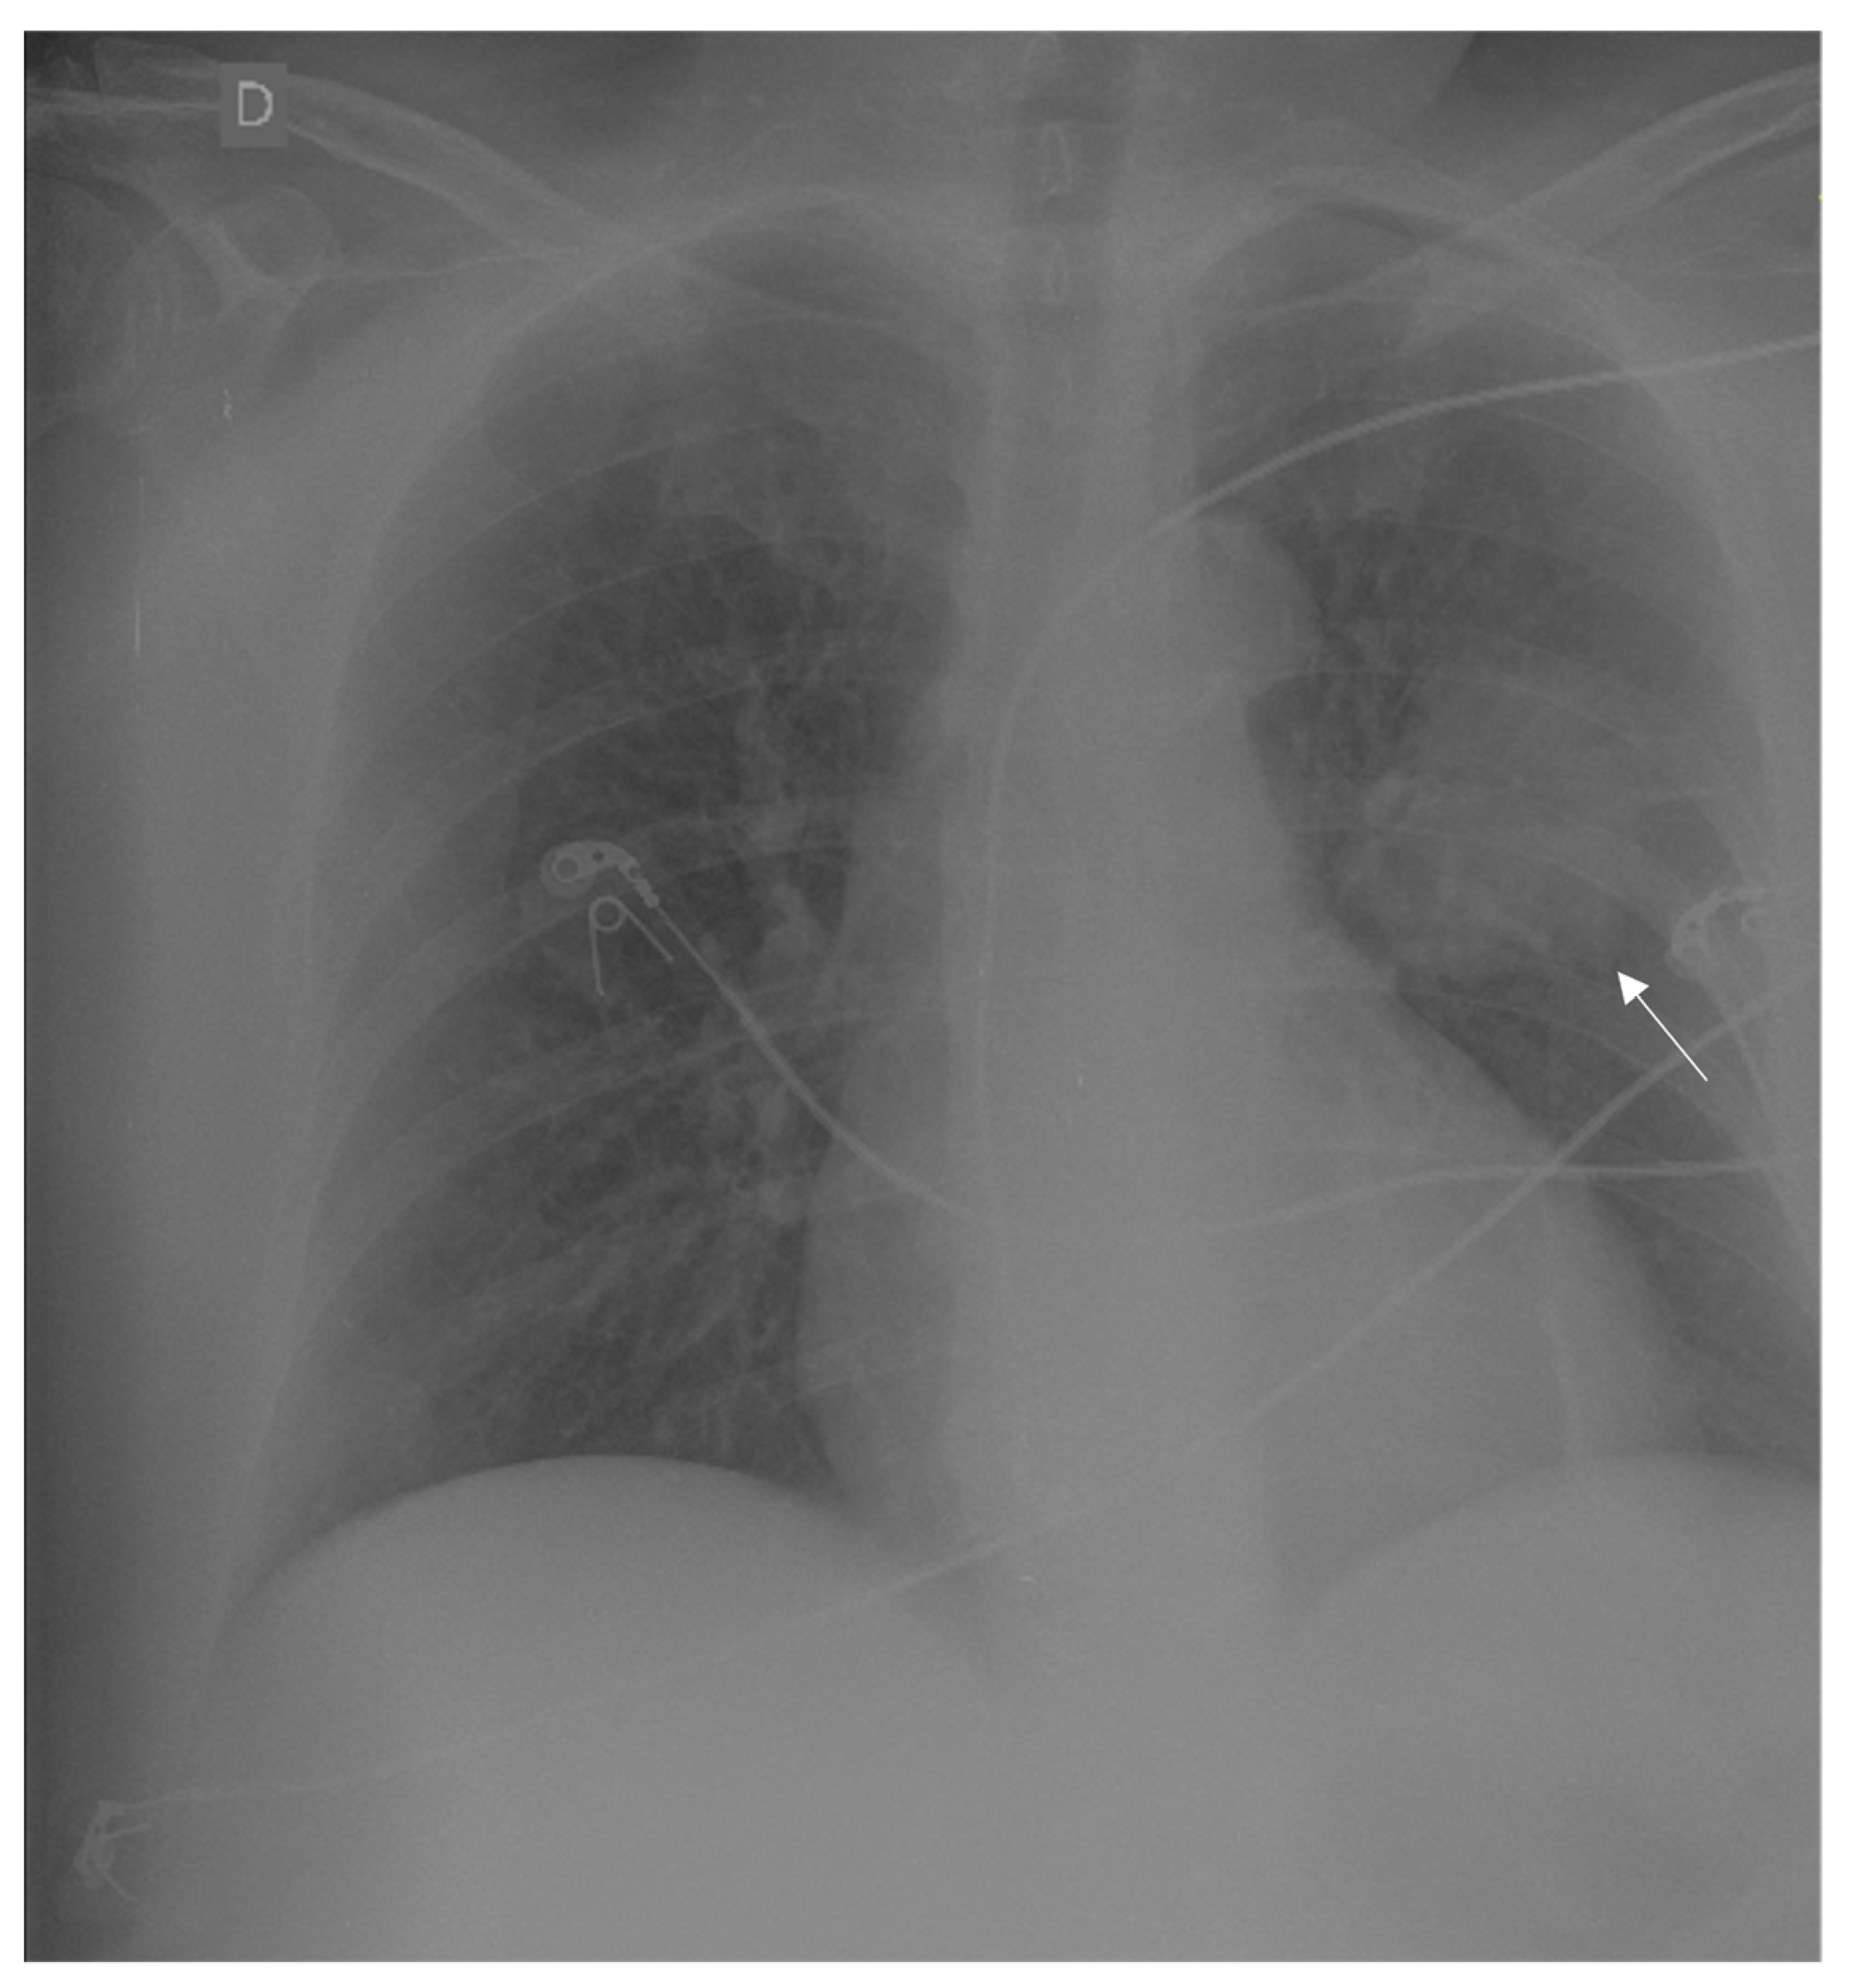

A female, sixty-year-old patient presented with syncope, a history of headache, paresis in the right side of the body, and an occipital bulge with progressive growth in the past nine months. After being admitted to the first hospital, she underwent a chest x-ray that showed a pulmonary mass on the left side (Figure 1). Regarding clinical history, the patient was an ex-smoker with a smoking load of 1 pack/year for 40 years, with systemic arterial hypertension, dyslipidaemia, and a history of an acute heart infarct treated with stent placement 2 years before. No further investigation was performed at that time. She was then transferred to the Instituto Estadual do Cérebro Paulo Niemeyer (Rio de Janeiro, Brazil) for further evaluation and surgical programming.

Figure 1.

Chest X-ray showing a round mass in the upper lobe of the left lung (indicated with an arrow) suggestive of lung cancer (D in the image means right side).